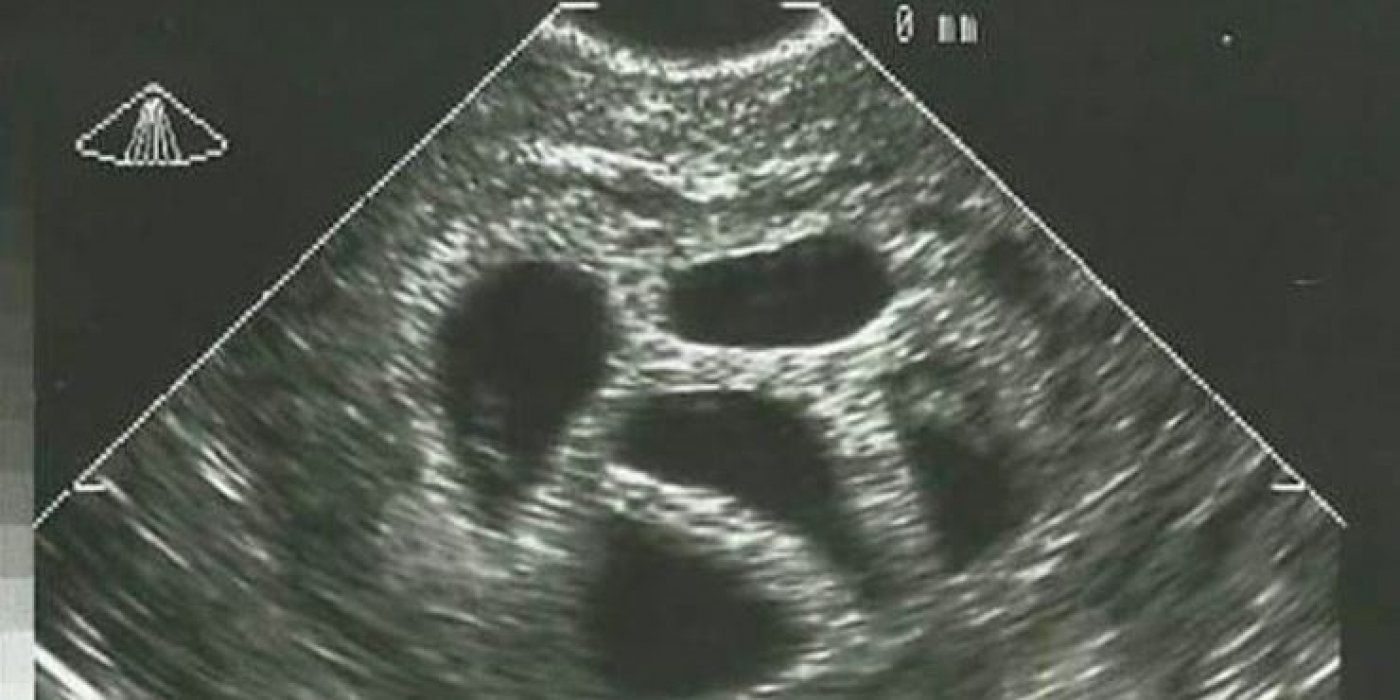

“U dobi od 28 godina saznala sam da sam trudna i to s petorkama. Moj liječnik odmah mi savjetovao selektivni pobačaj, prenosi Narod hr.

Kad sam to odbila, poslao me ginekologu koji mi je u više navrata sugerirao da razmislim o “smanjenju broja” začete djece u mojoj maternici. Predlagao mi je da pobacim troje ili čak dvoje djece. To je trajalo nekoliko mjeseci.